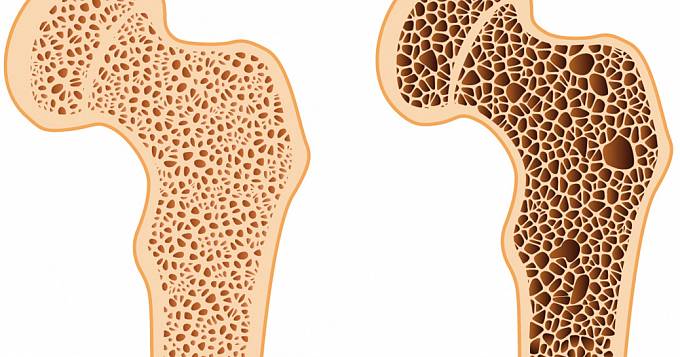

- Остеопороз. Возникает из-за нехватки кальция в костной ткани. На ребрах могут образовываться трещины и переломы (при резких движениях), сопровождающиеся резкой болью, которая не проходит в покое.